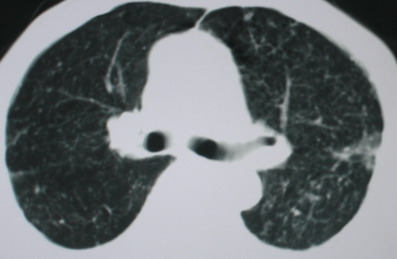

以下是引用卜一在2008-6-3 19:33:00的发言:[br]双肺结节,以双上肺分布为多,期间搀杂片状致密影及索条致密影。考虑:继发性肺结核伴血型播散可能性大。不除外肺泡ca的可能!另:椎体退变!

以下是引用panyishengct在2008-6-3 21:09:00的发言:[br]双上肺弥漫性小结节影,纵隔窗内钙化淋巴结影,考虑矽肺或/和tb可能性较大,不除外肺ca可能。腰椎考虑退变。 [br][br]